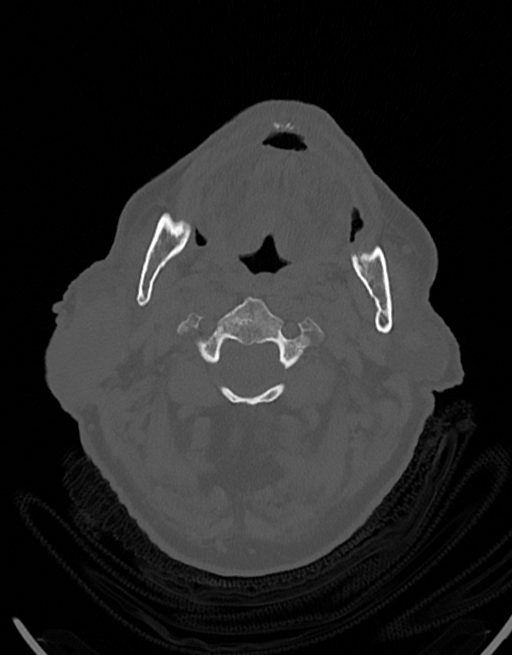

در سي تي اسکن اسپيرال نازو فارنکس با و بدون کنتراست (مولتي ديدکتور 16 با مقاطع ظريف و بازسازي هاي ساژيتال و کرونال):

– توده نسج نرمي به ابعاد mm 40 x 45 x 60 در ناحيه پاروتيد راست، با enhancement هتروژن پس از تزريق کنتراست مشهود است که مطرح کننده آدنوم پاروتيد مي باشد.

– شواهدي از تهاجم توده به استخوان و عروق اطراف مشهود نيست .

– کلسيفيکاسيون در ديواره شريان هاي کاروتيد دو طرف مشهود است .